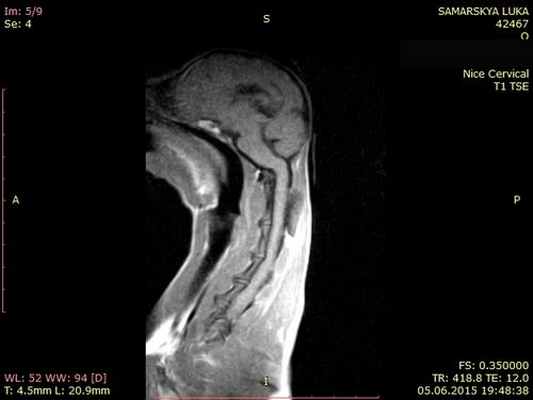

МРТ краниовертебрального сочленения в сагиттальной плоскости (А) и художественное исполнение (Б).

Показаны покровная мембрана (стрелка) и поперечная связка атланта (толстая стрелка).

БА — базион; ОП — опистион; ПМем — передняя атланто-затылочная мембрана; ЗМем — задняя атланто-затылочная мембрана;

З—Зуб; Ост2 — остистый отросток С2;ПД — передняя дуга атланта (тонкая стрелка); ЗД — задняя дуга атланта. Крестообразная, поперечная, крыловидные и добавочные связки.